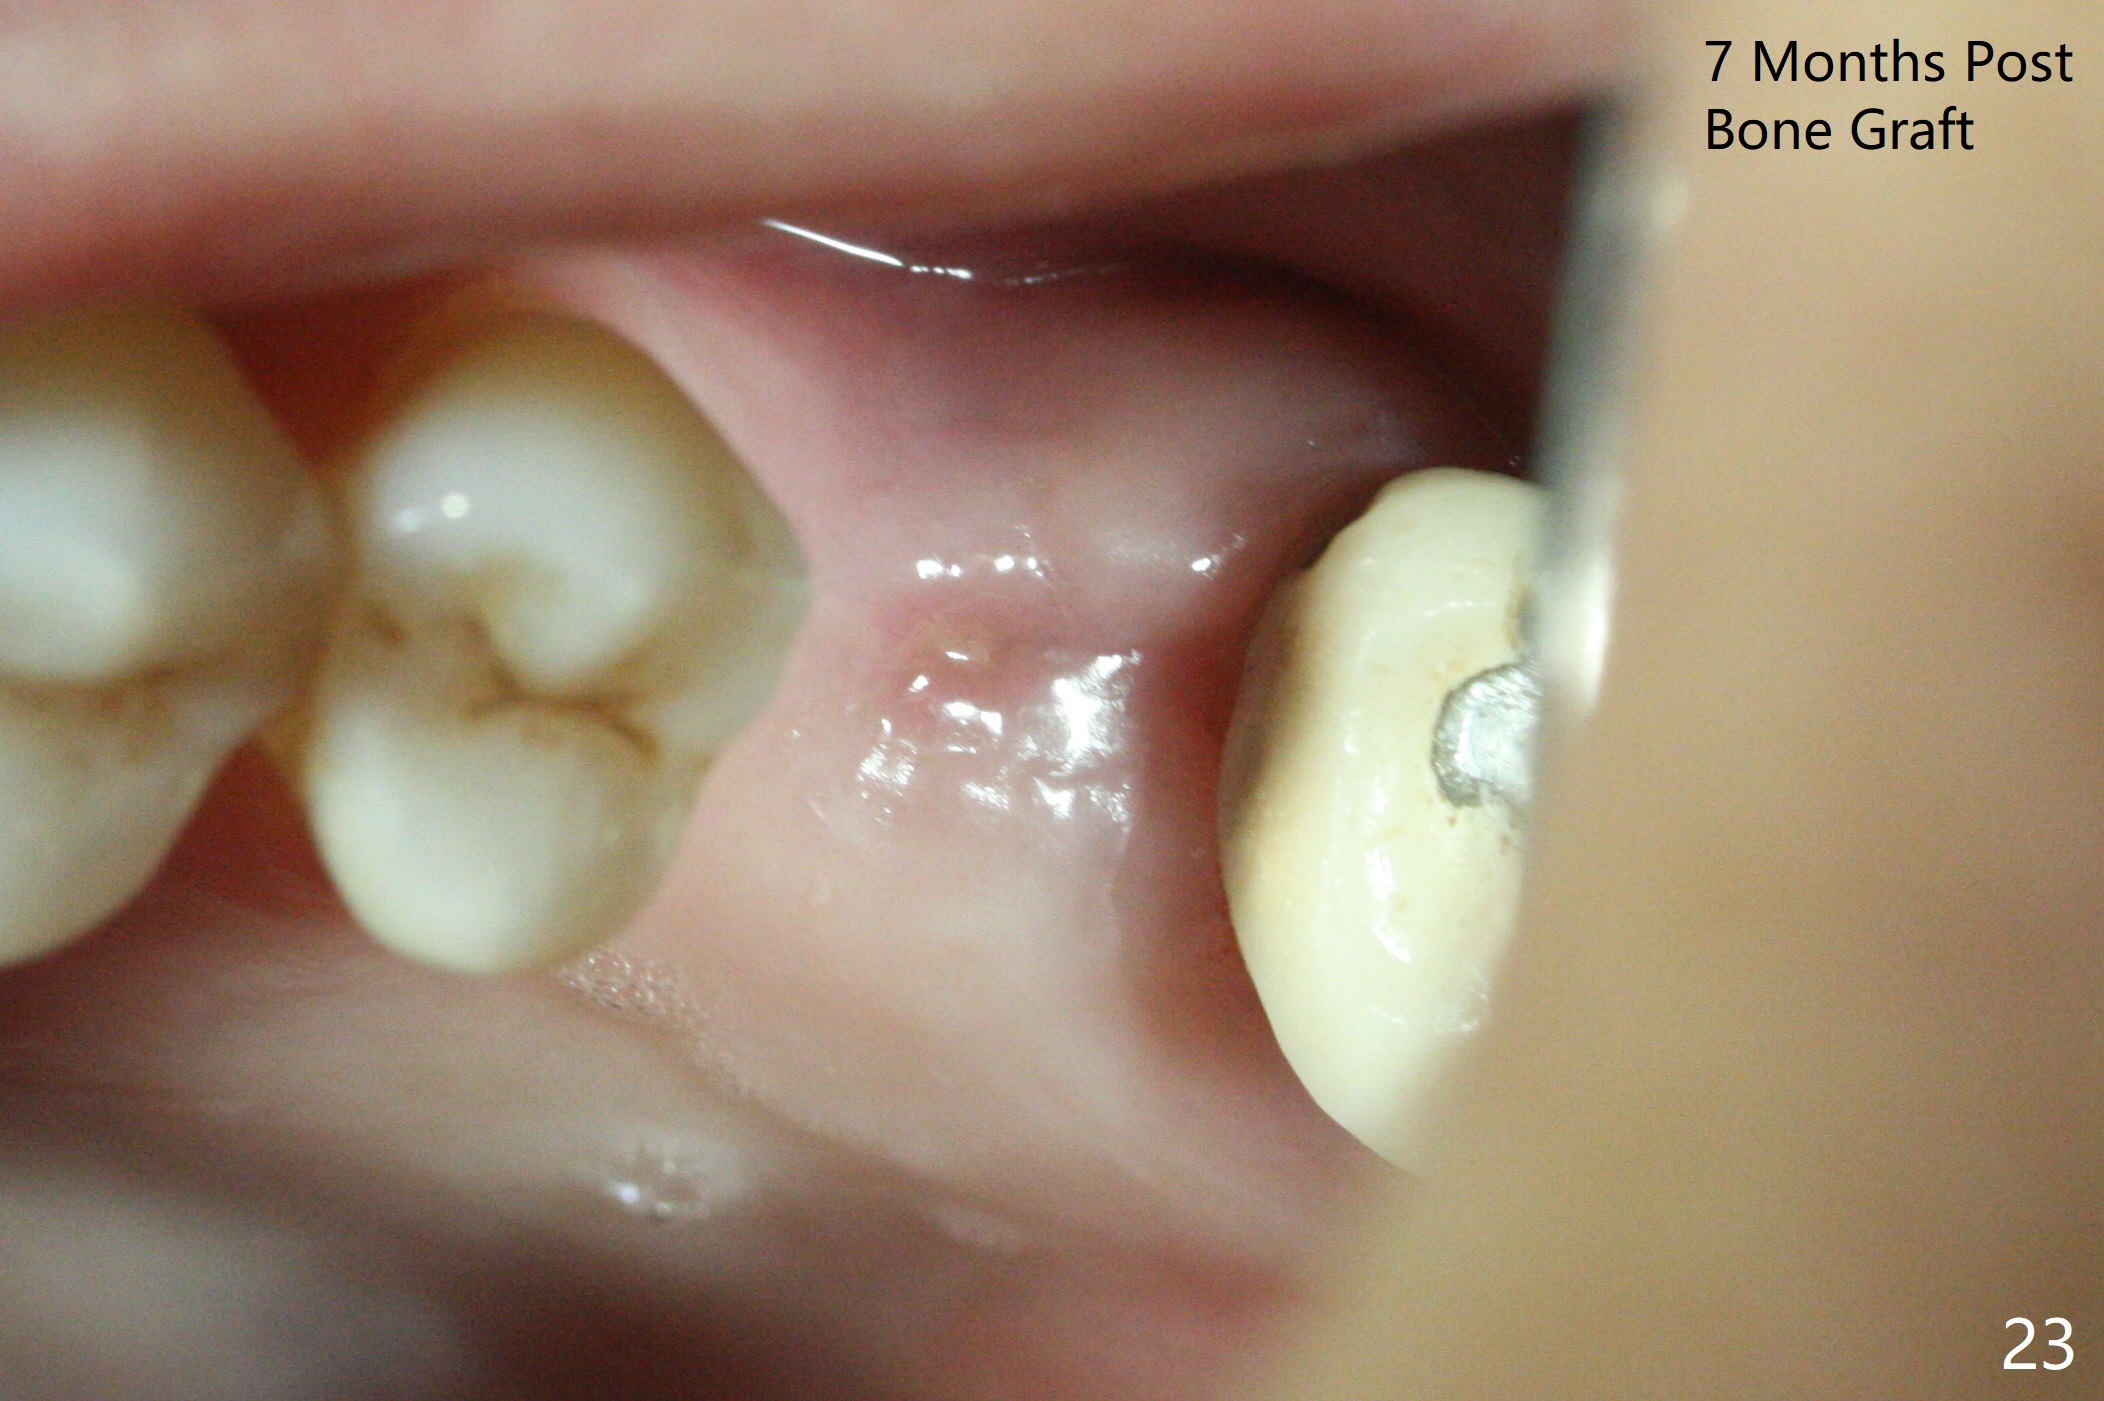

The implant is stable 8 months postop (Fig.15). When a 6x4(3) mm abutment is placed 8.5 months postop, it is distal (Fig.16). The mesiodistal width is 1-2 mm shorter than that at #3, which suggests the mesial shift of the tooth #15. A provisional is fabricated at #14 (Fig.17 P) with supra-occlusion so that there is clearance between the tooth #15 and the opposing one (Fig.18 *). With a separator placed between #14 and 15 (Fig.19), the latter is free to be distalized. Bone volume and density seem to increase 4.5 and 10.5 months post cementation (Fig.20,21, as compared to Fig.15), although the buccal plate remains as concave as shown in Fig.18. One year 5 months post cementation, the patient complains of bad smell from the implant when water pik is being used. It appears that the 1st 2-3 threads are exposed (Fig.22), although the surrounding gingiva remains uninfected. Bone graft is recommended. The site heals without bad smell 7 months post bone graft (2 years 4 months post cementation, Fig.23). The 1st implant thread is found exposed buccal on uncover (regraft?). A small healing abutment is placed because the implant is placed distal (Fig.24). An angled abutment should be tried and #15 crown will be redone. Impression will be taken when the gingiva heals around the provisional crowns.